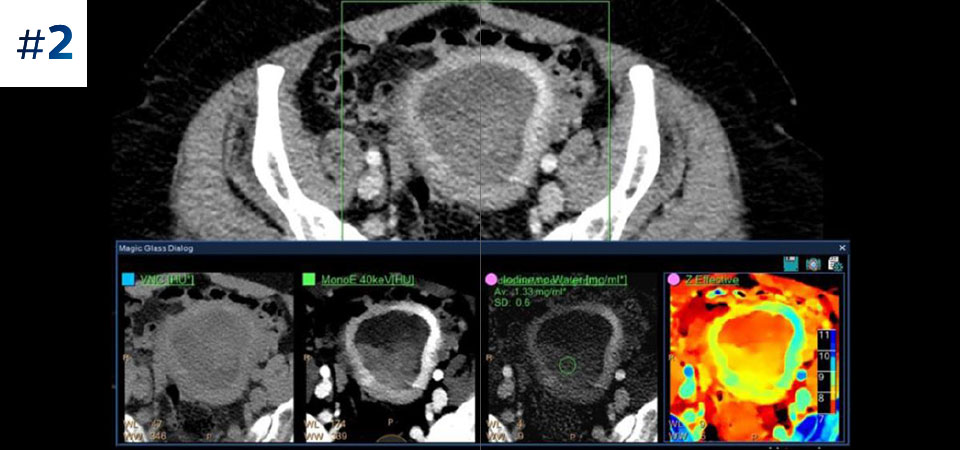

With detector-based spectral, you acquire multiple layers of data—conventional and spectral—within a single exposure and without special scan modes for improved tissue characterization and visualization.

Scan as usual A single scan for fast, low-dose conventional and spectral data for every patient, every time.

Always available 100% spectral, 100% of the time for results that are always available on-demand, even retrospectively.

Reduced follow-up exams Improved tissue characterization and visualization may reduce the need for follow-up scanning for sub-optimal exams and incidental findings.